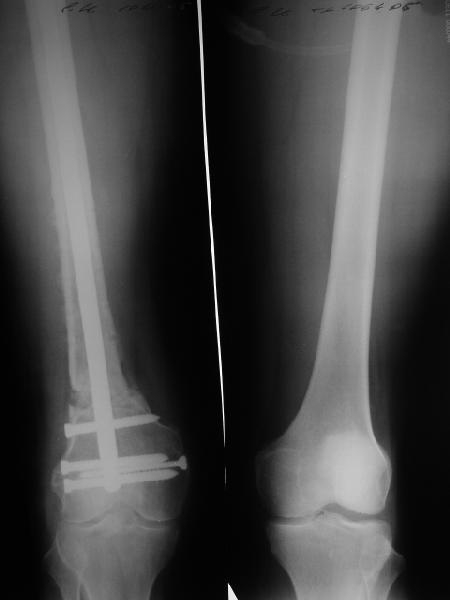

К нам больной поступил с признаками ложного сустава бедренной кости, перелома

штифта и дистального блокирующего винта (images 1,2,3).

27 марта выполнено удаление блокирующих винтов (сломанный винт пришлось высверливать цапфен-бором), сломанного штифта (дистальный фрагмент удален через канал, образованный разверткой из коленного сустава - image 4),

рассверливание костно-мозгового канала, реостеосинтез штифтом UFN (при проведении штифта в дистальном отломке мы использовали поляризующий винт, диаметр штифта 10 мм). После операции в связи гемартрозом дважды (на 1 и 3 сутки) выполняли пункцию коленного сустава. Сейчас признаков скопления жидкости в полости сустава нет. Послеоперационные рентгенограммы - images 5, 6, 7.